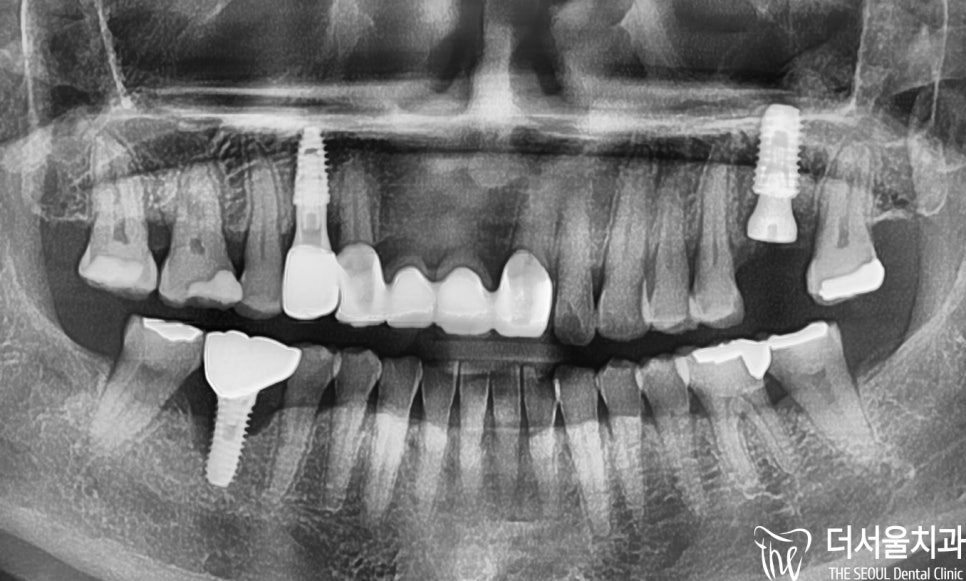

잠실 치과 에서 파노라마(X-Ray) 촬영을 진행했는데요.

# 14, # 26 소구치 및 대구치에

치주염으로 인한 골소실이

나타난 것을 볼 수 있었습니다.

다들 골소실이 어느 정도 있었기에

뼈이식을 해줄 수밖에 없었는데요.

잠실 치과 는 먼저 # 14 임플란트 식립 후,

# 26이 회복되고 뼈이식을 통해 잘 굳어졌을때,

픽스처를 심어드렸습니다.

파노라마와 육안으로 보여지듯

보철 수술은 무사히 잘 끝났습니다.